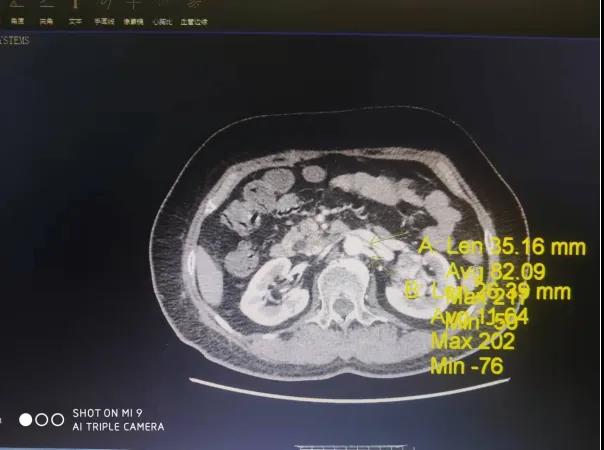

患者,女性,61岁,因体检发现左肾肿物一周收入院,入院后行全腹部增强CT检查回报:左肾下极肿瘤。大小48*47mmhg,肿瘤分期:T1bM0N0,肿瘤位于肾实质深部,上极紧贴肾门,各期影像显示患肾血供复杂:包括肾动脉、副肾动脉各一支。

肾静脉两支

变异血管分布如下:

第四腰椎椎前血管发出的侧支动脉一支

穿过后腹膜入肾上极变异动脉一支(来源于脾动脉)

肿瘤回流静脉一支(内有癌栓)